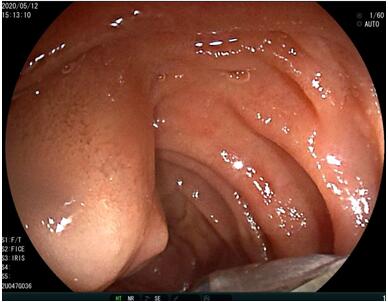

69歲王姓患者,因“發(fā)現(xiàn)無痛性黃疸1月”入院,根據(jù)患者病史,患者診斷傾向于壺腹部腫瘤所致梗阻性黃疸。予以完善腹部CT及上腹部MRI加MRCP均顯示肝內外膽管擴張,未發(fā)現(xiàn)明顯膽管,胰腺及十二指腸乳頭部腫瘤,且患者CA199正常。以前醫(yī)院未引進超聲內鏡,這類患者到此就遇到診斷瓶頸。此患者經過消化內科張丹霞副主任醫(yī)師完善超聲內鏡檢查后,可以清楚顯示膽總管下段壁內軟組織占位?;颊咄ㄟ^超聲內鏡檢查診斷明確,轉至肝膽外科行手術治療。

環(huán)掃超聲內鏡主要用于胃腸道粘膜下腫物診斷,胃腸道腫瘤分期,發(fā)現(xiàn)早期胃癌等,扇掃超聲內鏡主要用于診斷膽道及胰腺疾病,并且可行穿刺活檢取病理。